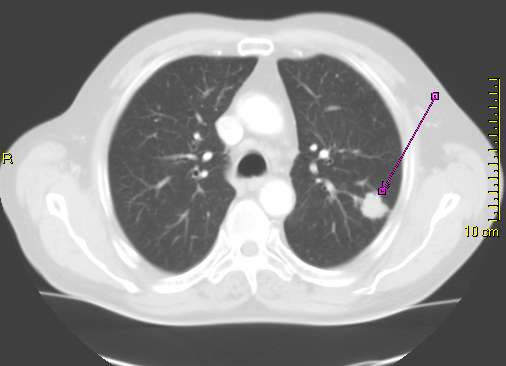

폐암은 흉부 X-RAY 검사나 컴퓨터단층촬영(CT)을 통해 종양의 여부, 크기, 위치를 평가하여 진단한다.[52] 흉부 X-ray 검사는 폐 안의 종양 덩어리를 확인하는 데 사용되며, 종격동 확장, 무기폐(폐의 일부가 팽창된 상태를 유지하지 못하고 부피가 줄어든 상태[53]), 폐경화, 흉막 삼출 등을 판독할 수 있다.[48] CT 검사는 종양의 크기와 위치를 더 정확하게 판독하는 데 사용된다.[52][48]

흉부 방사선 촬영 사진이나 CT 스캔에서 폐암은 종종 폐결절로 나타날 수 있다. 폐암 검진을 받은 사람 중 약 30%가 폐결절을 가지고 있으며, 그 중 대부분은 양성이다.[60] 폐암 외에도 과오종, 감염성 육아종 등 다른 질환에서도 폐 결절 증상이 나타날 수 있다.[62]